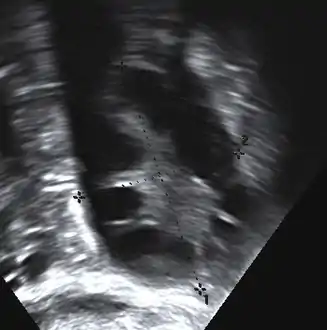

The syndrome acquired its most widely used name due to the common sign on ultrasound examination of multiple (poly) ovarian cysts. These "cysts" are in fact immature ovarian follicles. The follicles have developed from primordial follicles, but this development has stopped ("arrested") at an early stage, due to the disturbed ovarian function. The follicles may be oriented along the ovarian periphery, appearing as a 'string of pearls' on ultrasound examination.[79]

Transvaginal ultrasound scan of polycystic ovary

- Gynecologic ultrasonography, specifically looking for small ovarian follicles. These are believed to be the result of disturbed ovarian function with failed ovulation, reflected by the infrequent or absent menstruation that is typical of the condition. In a normal menstrual cycle, one egg is released from a dominant follicle – in essence, a cyst that bursts to release the egg. After ovulation, the follicle remnant is transformed into a progesterone-producing corpus luteum, which shrinks and disappears after approximately 12–14 days. In PCOS, there is a so-called "follicular arrest"; i.e., several follicles develop to a size of 5–7 mm, but not further. No single follicle reaches the preovulatory size (16 mm or more). According to the Rotterdam criteria, which are widely used for diagnosis of PCOS,[10] 12 or more small follicles should be seen in a suspect ovary on ultrasound examination.[21] More recent research suggests that there should be at least 25 follicles in an ovary to designate it as having polycystic ovarian morphology (PCOM) in women aged 18–35 years.[88] The follicles may be oriented in the periphery, giving the appearance of a 'string of pearls'.[89] If a high-resolution transvaginal ultrasonography machine is not available, an ovarian volume of at least 10 ml is regarded as an acceptable definition of having polycystic ovarian morphology. rather than follicle count.[88]